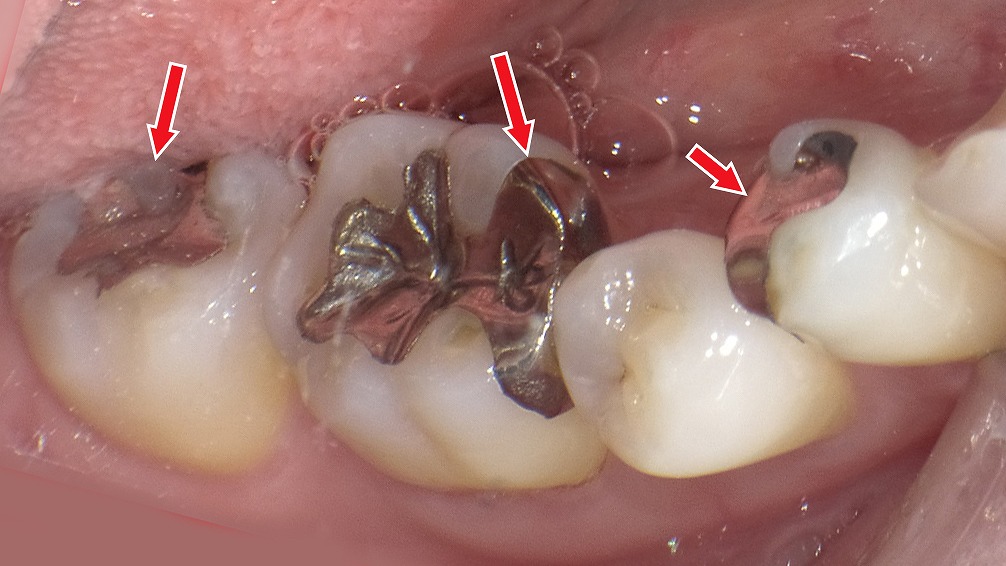

② 銀歯(金銀パラジウム合金)

銀歯は、保険適用で昔から使われている金属の詰め物。

強度があり、奥歯の噛む力にも耐えられます💪。

一方で、見た目が目立つ・金属アレルギーの心配がある点がデメリットです。